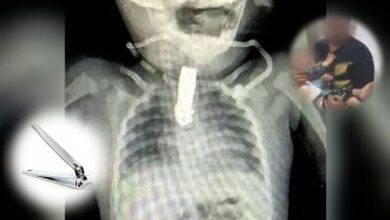

Bebé se tragó un cortaúñas y le quedó atorado en la garganta

Una bebé de ocho meses tuvo que ser operada de urgencia tras ingerir un cortaúñas por error. El suceso tuvo…